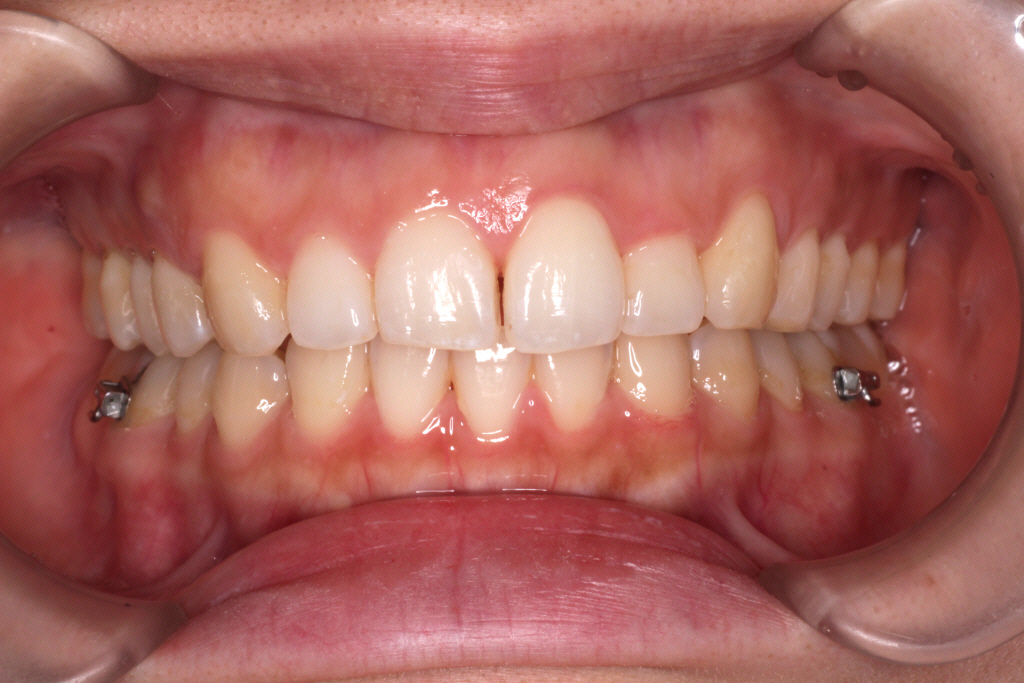

こちらが現在の口腔内写真です。